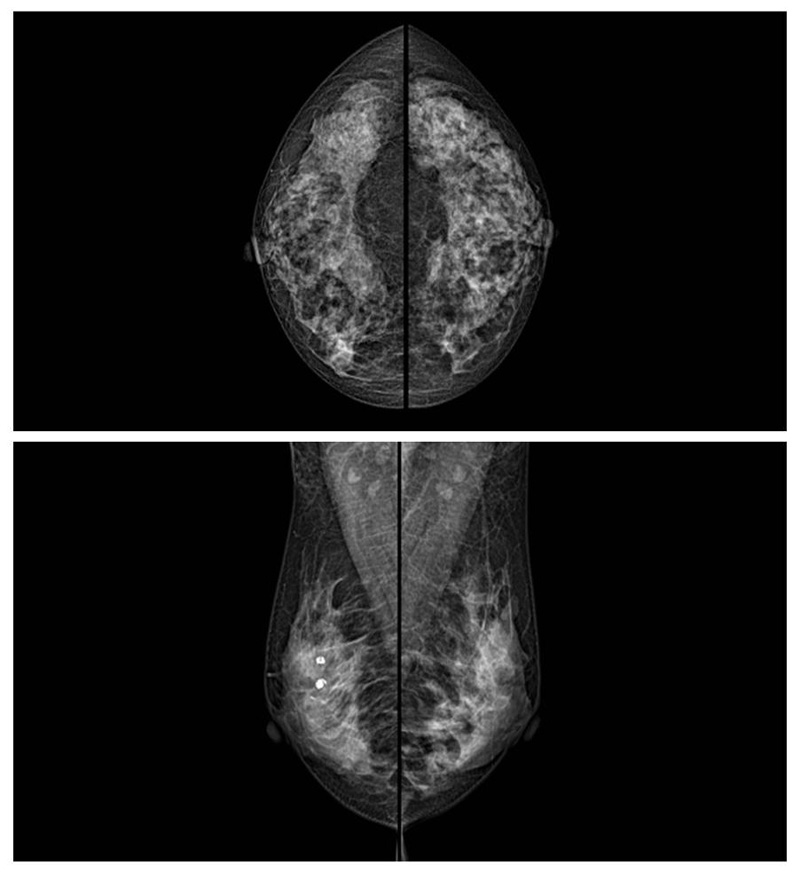

乳腺癌的發(fā)生率越來越高,已經(jīng)是我們國家的癌癥之一已成為女性健康“頭號殺手”。乳腺DR可提高乳腺癌早期檢出率并精準定位。發(fā)現(xiàn)和診斷早期乳腺癌最有效的方法之一,明顯利大于弊女性都要重視乳腺的檢查。輻射很小最簡便、最可靠、無創(chuàng)性檢查手段,做一次乳腺DR的劑量相當于7周的正常生活。尤其是對于40歲以上的女性尤為重要,那么乳腺DR是怎么進行檢查的呢?我們來了解一下,為廣大朋友在檢查前有點心理準備。檢查時候是避開經(jīng)期的前后,月經(jīng)來后的7天左右比較合適。需要脫衣服檢查,根據(jù)拍片的擺位要求,有頭尾位置,內(nèi)外斜位,還有側位。定點放大壓迫方法可以更細微清晰的檢查出病灶。